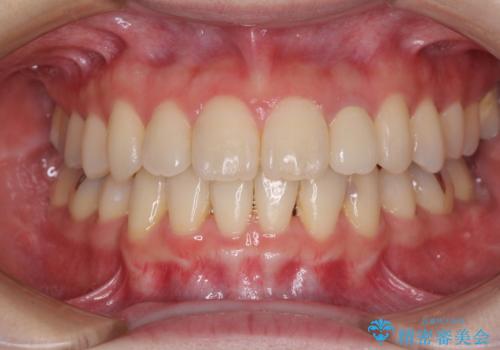

抜歯矯正は2年から2年半程度の治療期間を要することが一般的ですが、僅か1年1ヶ月で終了しました。

あっという間に気になっていた歯並びが改善し、患者様には大変満足していただきました。